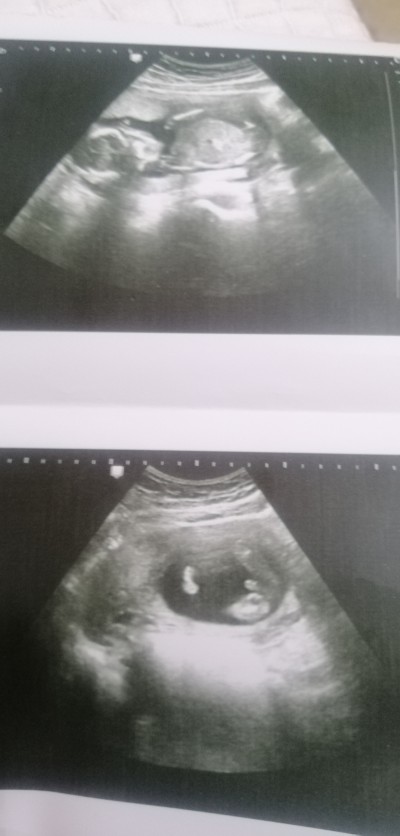

13 Aralık 2020 Hamilelik Dönemi Genel kategorisinde (18 puan) sordu

Gebelik haftası 16